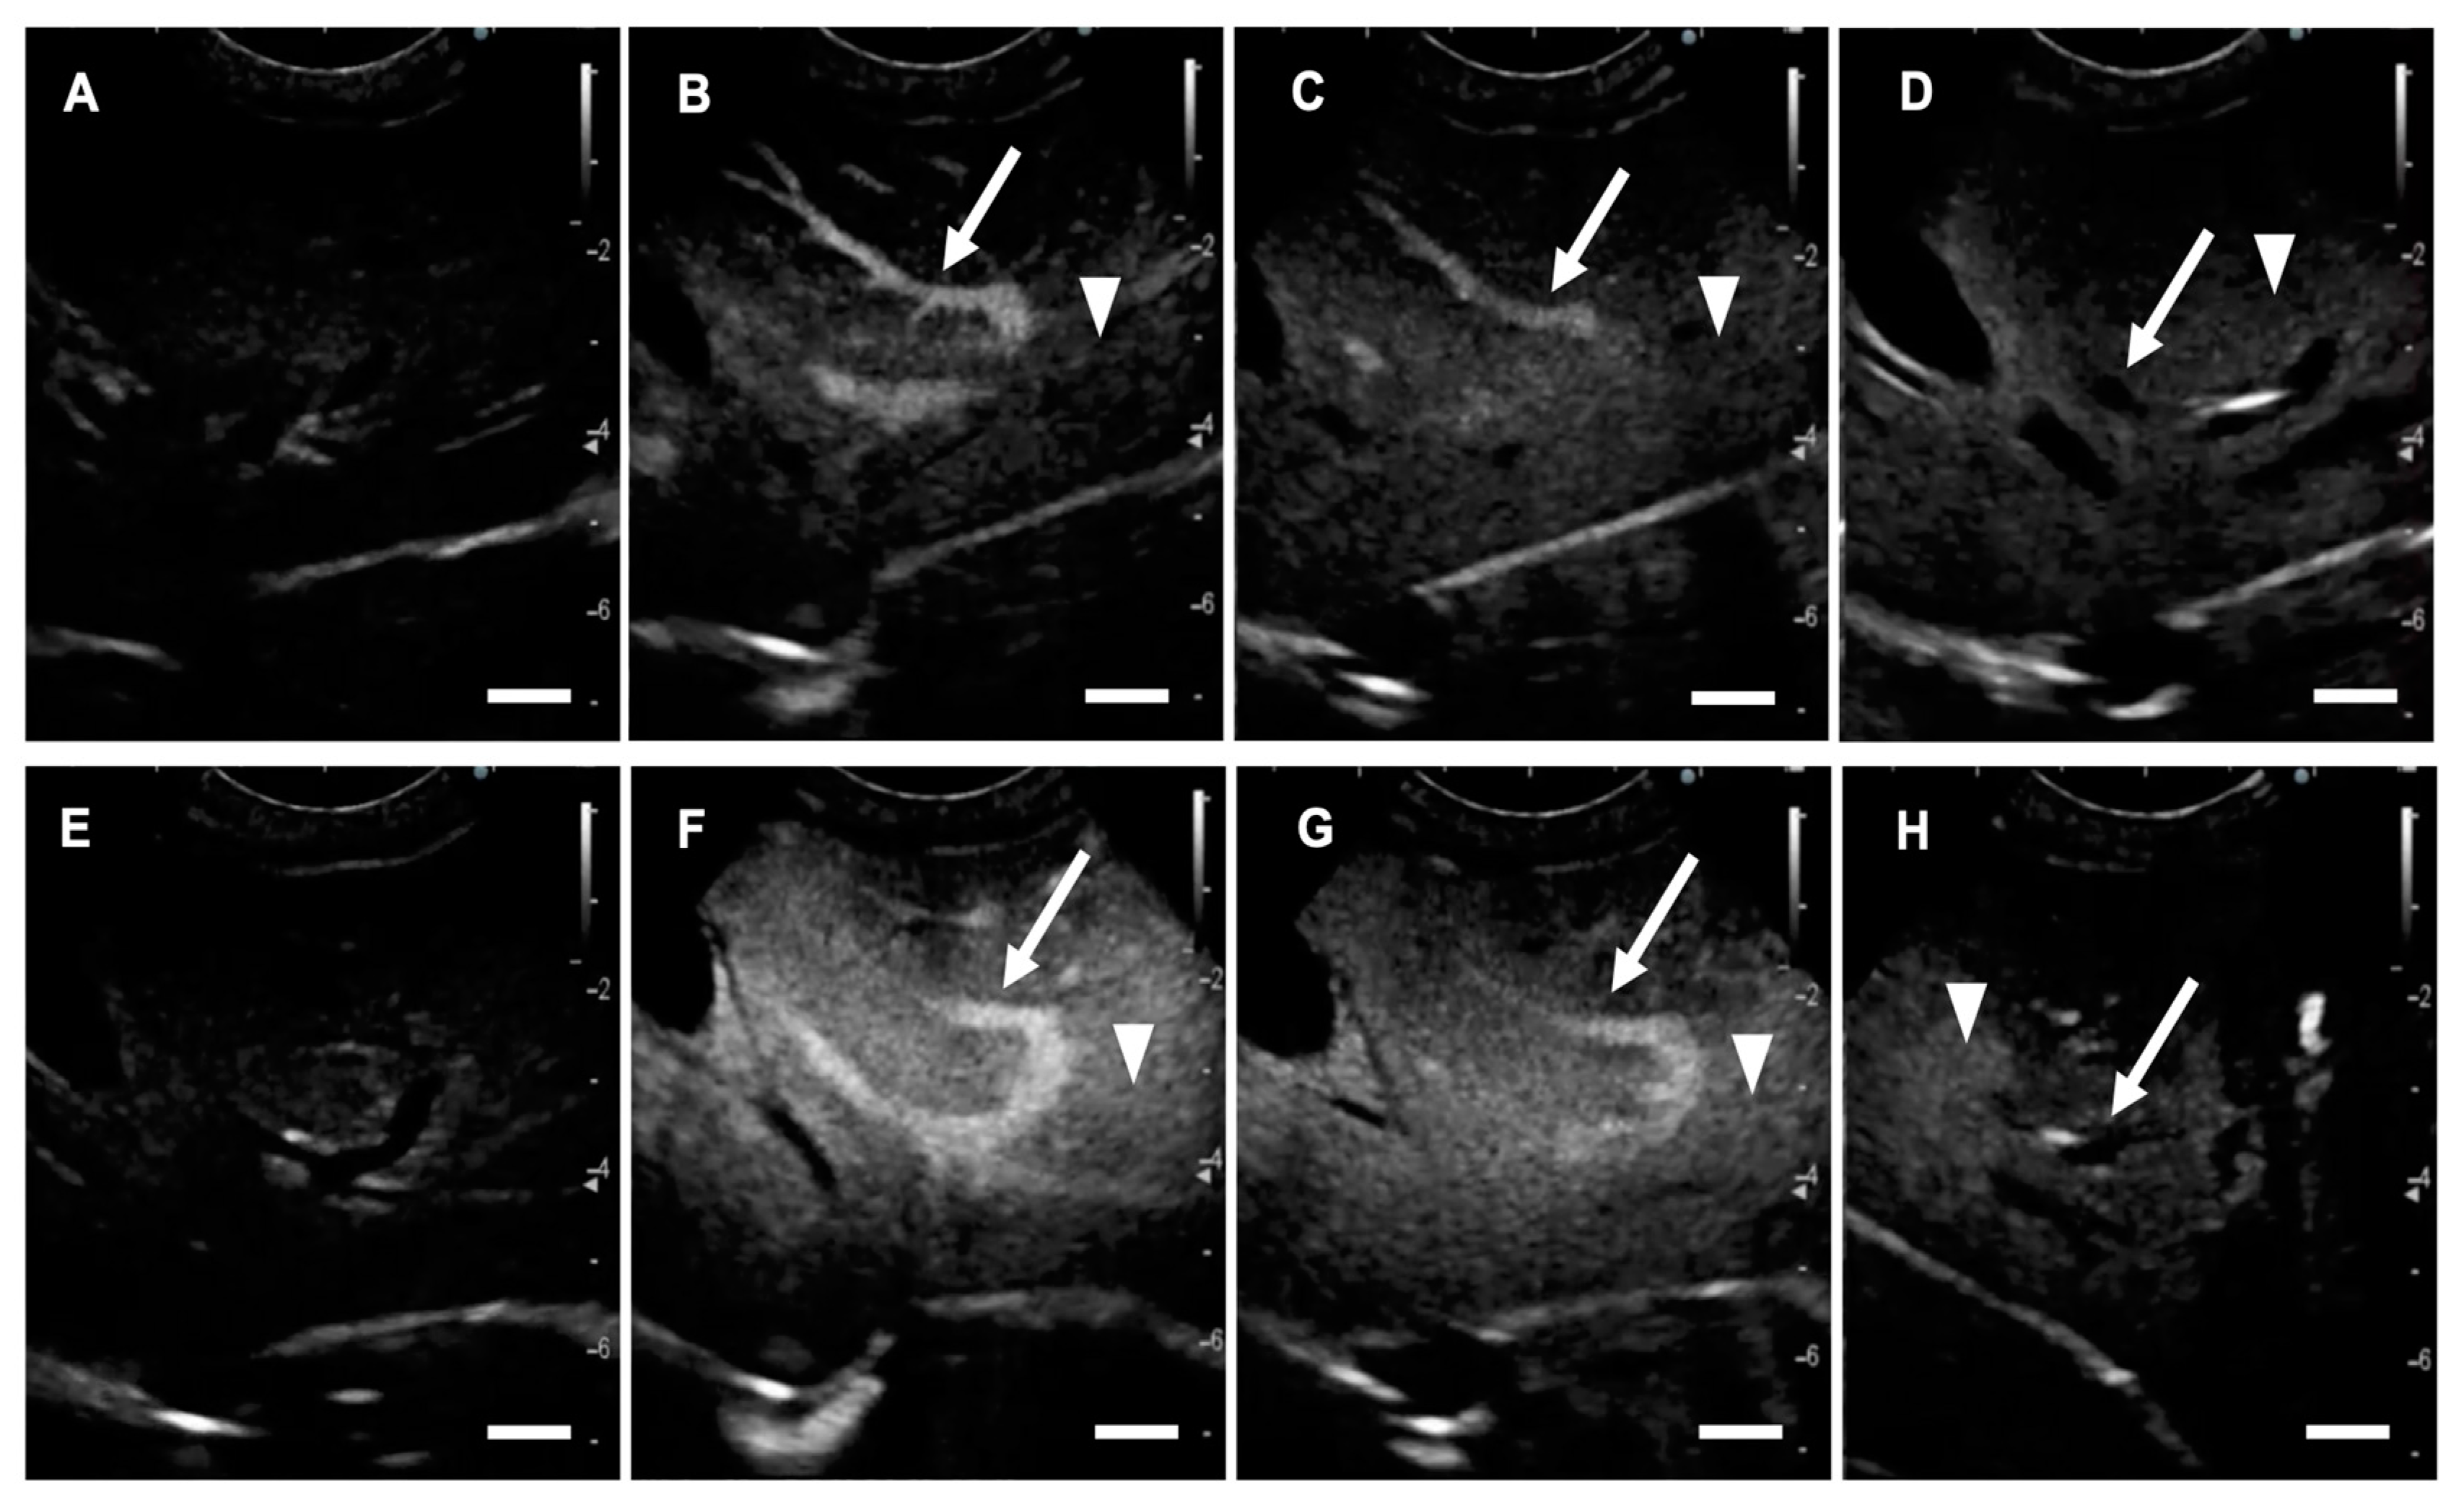

2.2. CEUS in Dogs with Focal Liver Lesions

4.3.3. CEUS Using LBs and Sonazoid

4.3.4. Evaluating the Diagnostic Accuracy of LB-CEUS